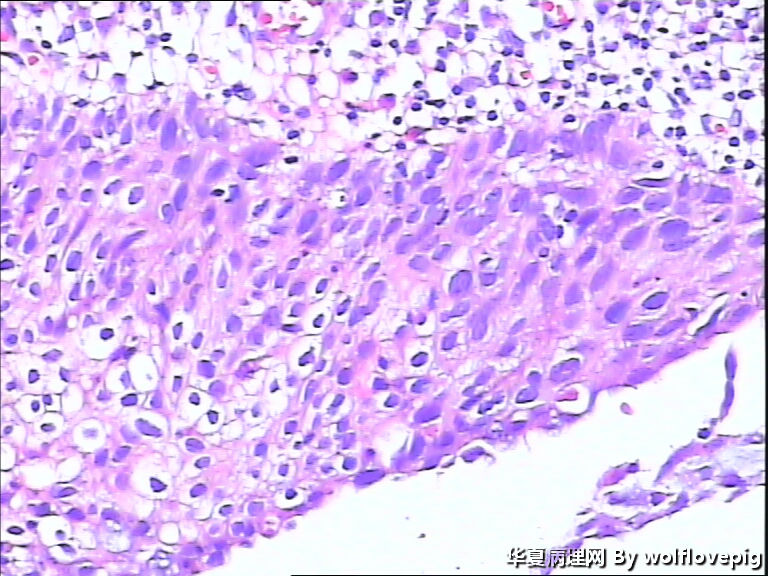

求助,宫颈!

37y

CIN3累腺

CINIII累及腺体

CIN-II 累及腺体。我看不够原位癌。学习了!

CIN2-3,累腺